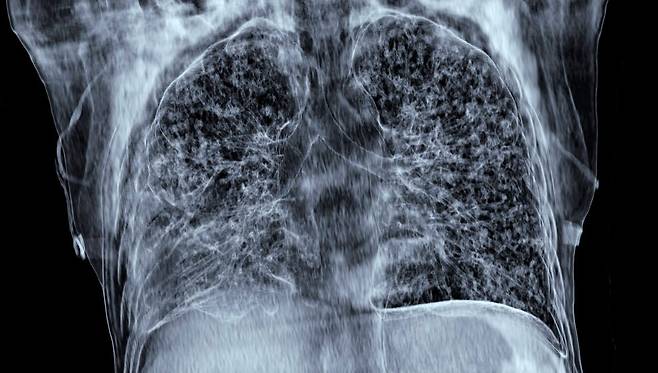

결핵이 의심돼 병원을 찾게 되면 우선 결핵 환자와의 접촉 유무를 확인하고 흉부 X선 검사를 진행한다. 결핵이 의심되는 소견이 보이면 결핵균에 의한 감염병인지 확인하기 위해 결핵균 가래 검사를 진행한다. 결핵균 가래 검사는 현미경으로 보는 도말검사법, 균을 키워 확인하는 배양검사법, 결핵균 유전자를 확인하는 결핵균 PCR 검사법 3가지가 모두 진행된다. 결핵은 대부분 약물로 치료하지만, 증상이 심하면 수술이 필요할 수도 있다. 치료 기간은 환자의 상태에 따라 6개월에서 12개월가량이 소요된다. 다제내성결핵은 치료 기간만 2년 가까이 소요되기도 한다.